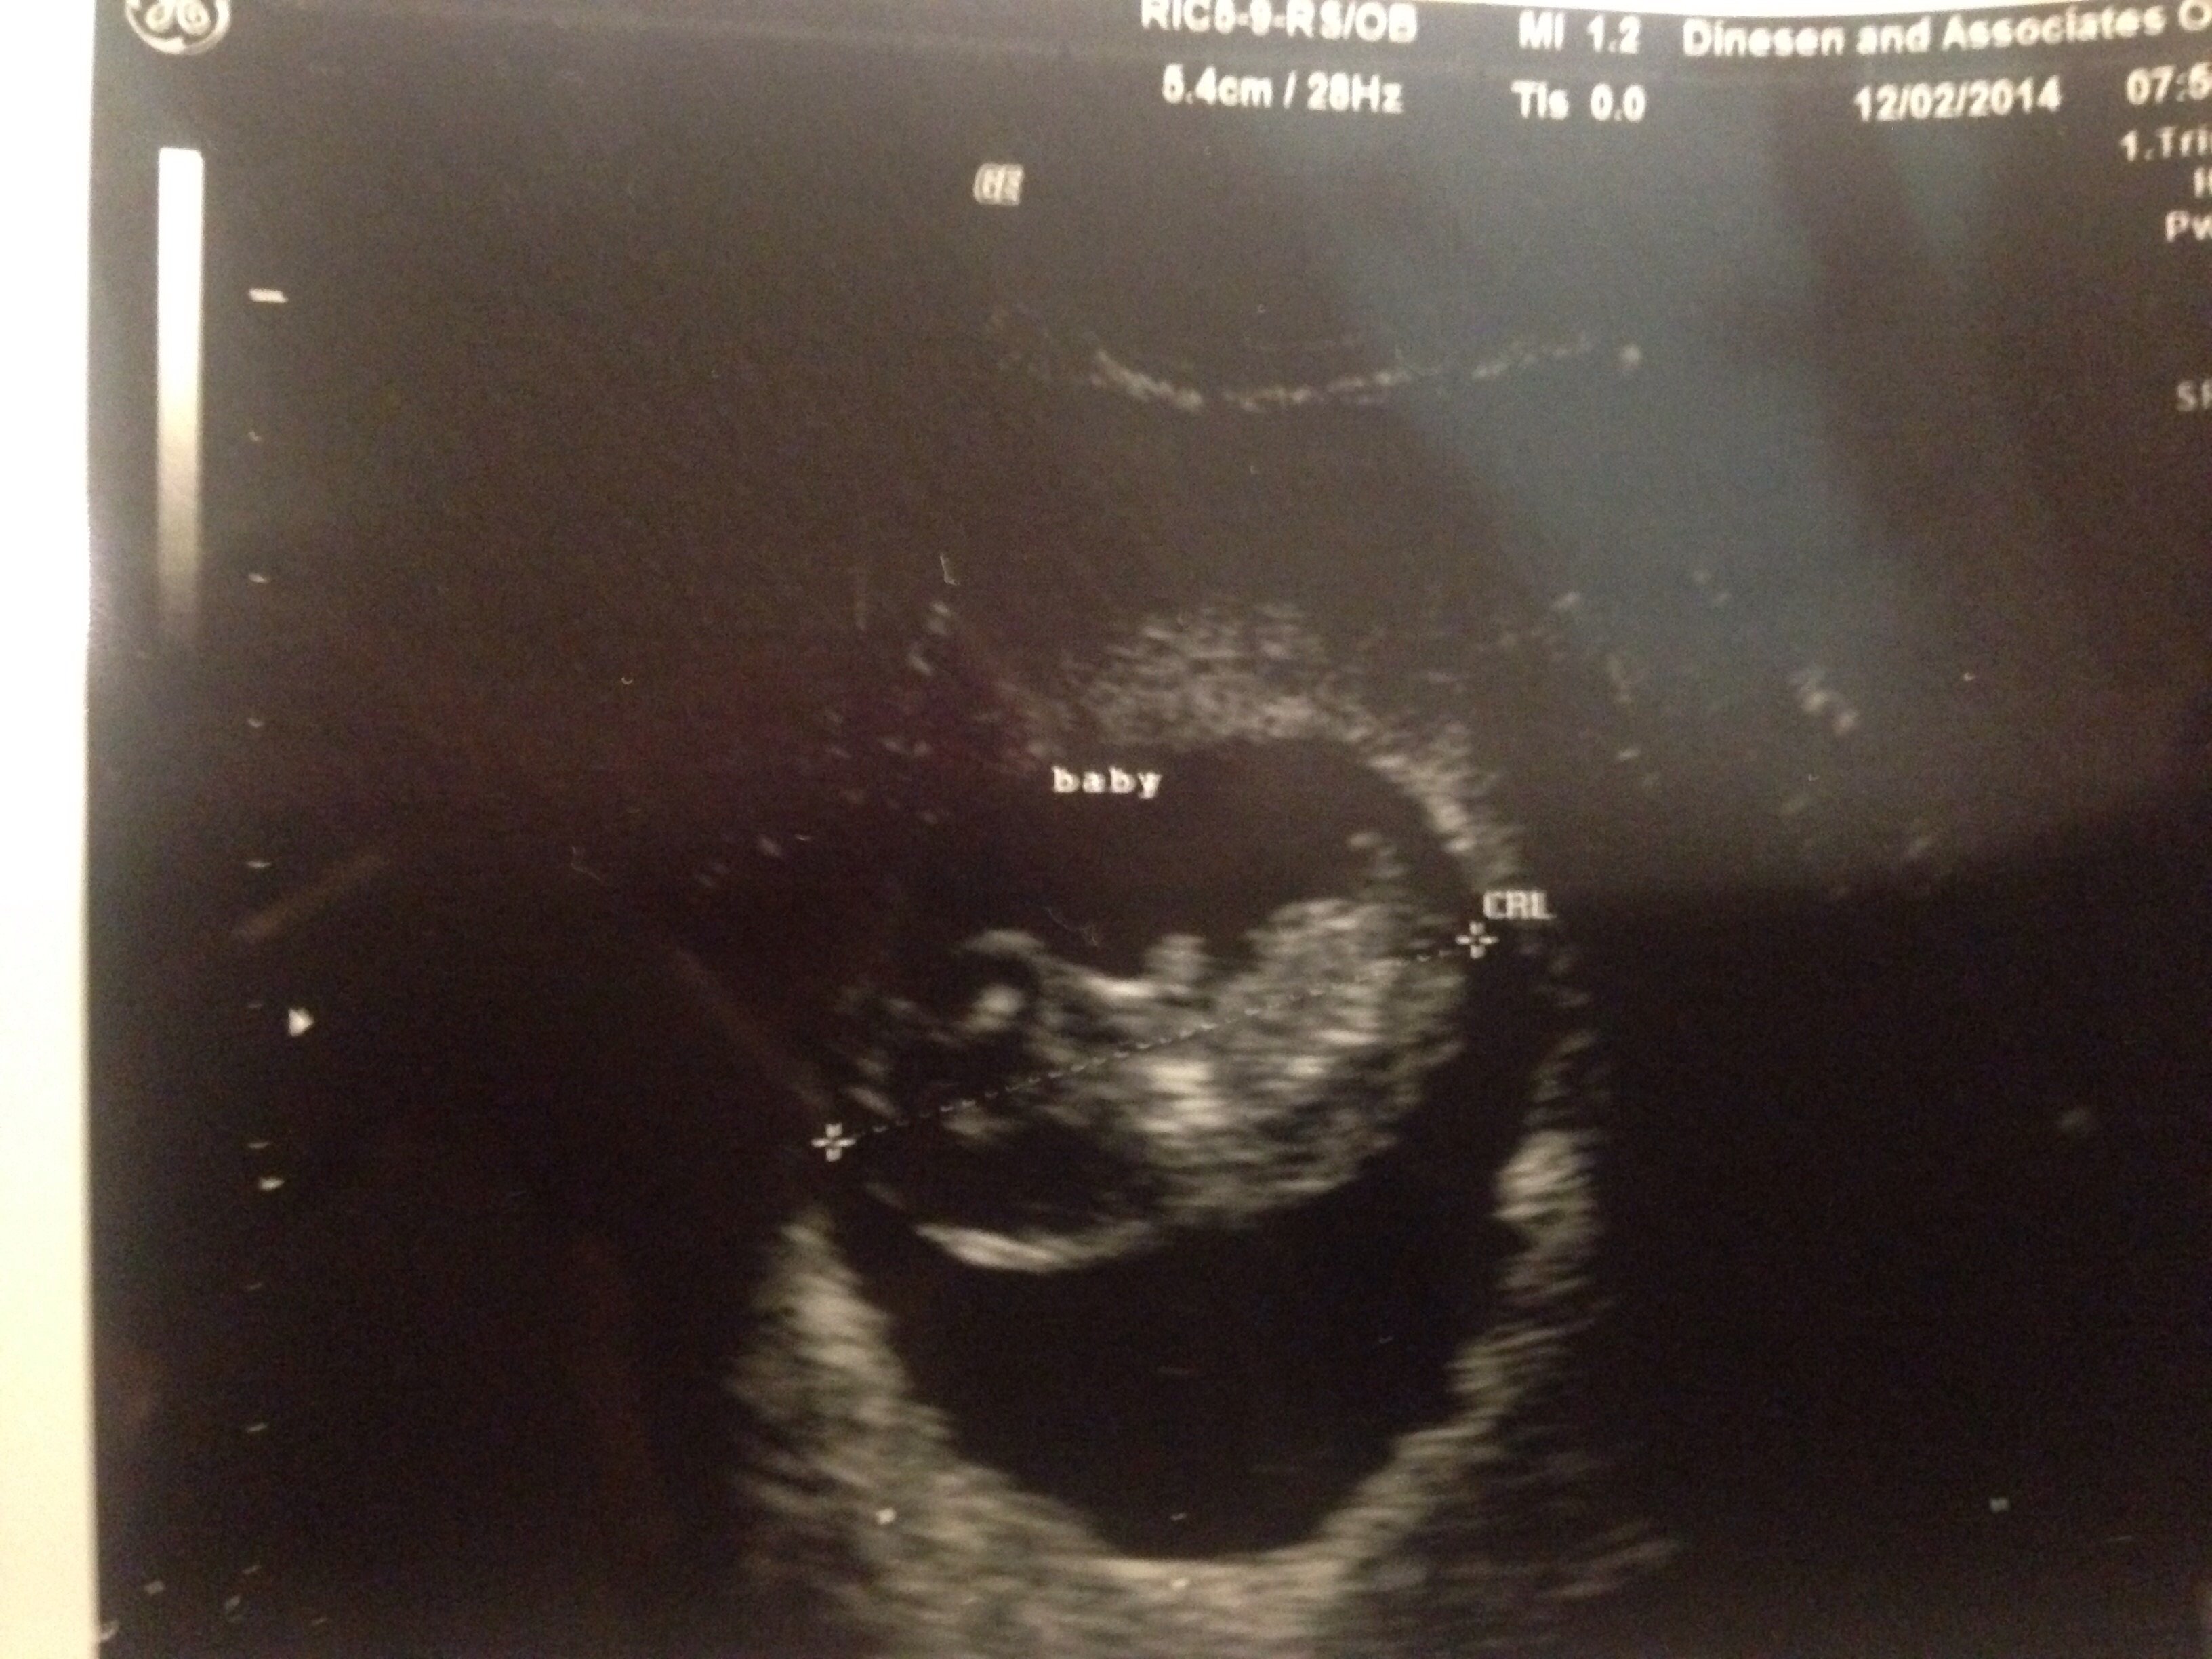

9 week ultrasound!

I had my second ultrasound today! My little nugget is measuring perfectly with a strong heart beat of 180, due 4th of July:). I'm so relieved because I've had break through bleeding around the time my period would have been due at 4 weeks and 8.